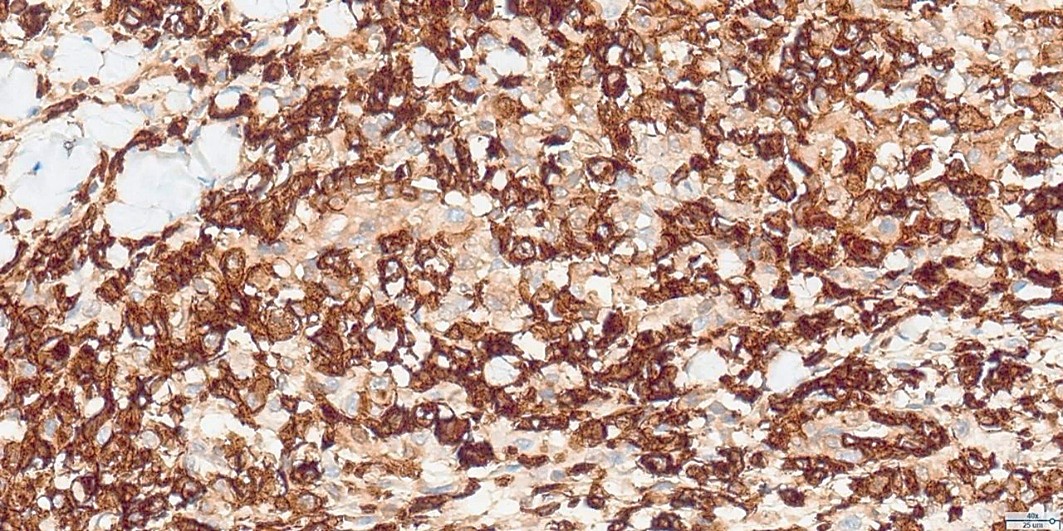

Histopathological examination revealed a non-circumscribed proliferation of large cells with marked nuclear pleomorphism, prominent nucleoli, and abundant clear cytoplasm, with numerous mitotic figures (Figure 3). Immunohistochemistry showed strong and diffuse expression of CD30 in atypical cells (Figure 4), and positivity for granzyme B, CD2, CD4, and CD25 in atypical T-cells (Figure 5). Numerous intermingled histiocytes were positive for CD68 and CD163, but negative in the atypical cells (Figures 6 and 7). ALK1 was negative in lymphoid cells (Figure 8). These findings supported the diagnosis of primary cutaneous anaplastic large cell lymphoma. Laboratory and PET-CT evaluation showed no extracutaneous disease. Localized electron beam radiotherapy was performed.

Figure 4: Immunohistochemistry for CD30 (40x): Strong and diffuse CD30 expression in atypical cells.